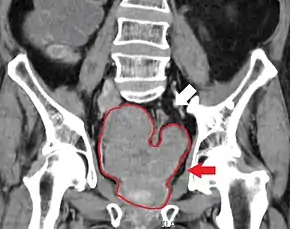

Prostate cancer that has metastasized to the lymph nodes

Prostate cancer that has metastasized to the bone

Prostate cancer is considered a malignant tumor because it can invade other areas of the body. This invasion is called metastasis.[94] Prostate cancer most commonly metastasizes to the bones and lymph nodes, and may invade the rectum, bladder, and lower ureters after local progression.[95] The route of metastasis to bone is thought to be venous, as the prostatic venous plexus draining the prostate connects with the vertebral veins.[96]